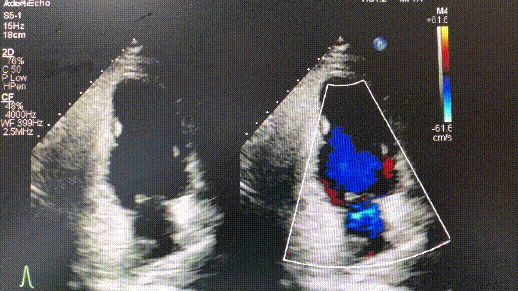

心脏瓣膜动图,心脏瓣膜图形

平时没症状体检却发现心脏的血"倒着"流?一定要开刀吗

功能良好(视频2-3),从4d-ct可以直观地看到心脏跳动情况下瓣膜的双层

主动脉瓣关闭不全图片

二尖瓣关闭不全